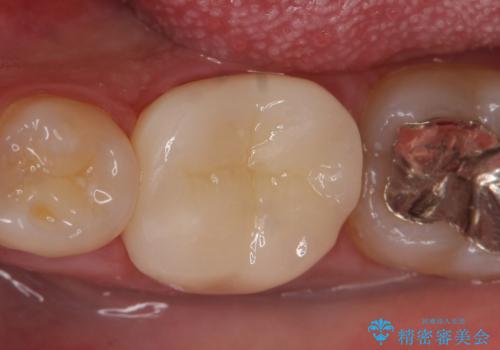

- 左下6の咬耗により歯がしみるている方の症例です。

オールセラミッククラウンによる補綴を行い、症状はなくなりました。

今回用いたオールセラミッククラウンは、ジルコニアフレームという白い素材の上にセラミックを盛っているため審美性が非常に高いのが特徴です。

またジルコニアは人工ダイヤモンドの材料にも使われているほど高い強度を持っており、そのためオールセラミッククラウンは審美性だけでなく、奥歯やブリッジの補綴も可能とするクラウンです。